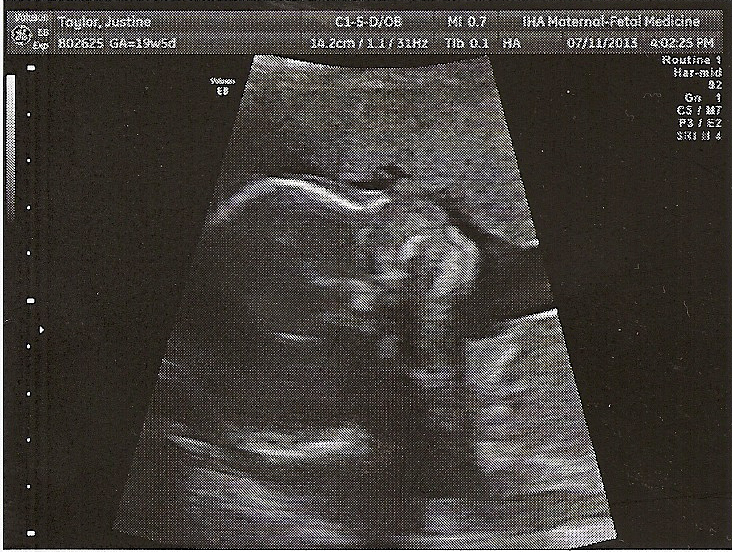

In July we had our big ultrasound, the one where we found out that Baby is a girl. For most of this one, she was all curled up, making the tech’s job pretty difficult. Here’s Lydia’s little sister when she was almost 20 weeks:

According to this ultrasound, Baby is big for her age, which is good considering the umbilical cord situation. It also supports Dan and my theory that the due date may be a little off. Most people expect their baby quite close to the due date, but with our suspicions combined with my history, we have no idea when Baby might surprise us!